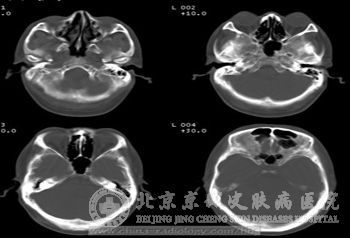

3、脑皮层结节,一旦病发结节性硬化症在大脑皮层出就会发生病变,有结节出现。

4、室管膜下结节或巨*星形*瘤,此病是一种遗传病,在病发过程中随疾病的发展有些组织*会形成结节硬块。

5、多发性室管膜下钙化结节伸向脑室,此病在病发时会波及全身大部分组织器官,所以脑部也会受到一定的影响。